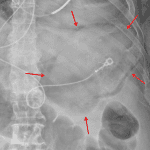

Indication: Concern for postoperative ileus

Findings

- Circumferential gas within the wall of the stomach

- Mild diffuse gaseous distension of loops of small and large bowel

- Retrocardiac pulmonary opacity

- Surgical drain overlies the anatomic pelvis

- Midline abdominal surgical staples

Diagnosis

- Gastric pneumatosis

Gastric pneumatosis of uncertain etiology. Recommend CT for further evaluation.

Mild diffuse gaseous distension of loops of small and large bowel, which may represent ileus. This can also be further evaluated with CT.

Retrocardiac pulmonary opacity, which can also be further evaluated with CT.